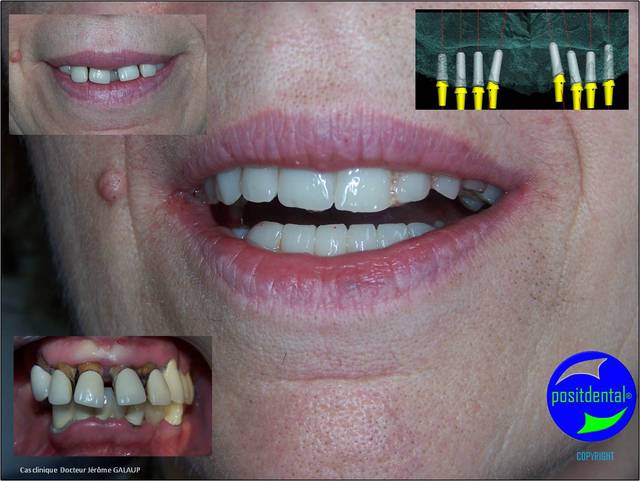

03/05/2011 à 17h47

photo pré opératoire

Wax up 3d positdental 13 qz0t5p - Eugenol